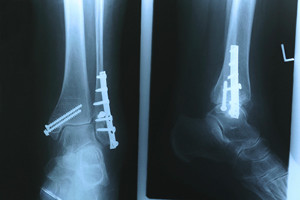

Treatment for broken bones varies depending on the cause, severity and location. Some will require the use of splints, casts or crutches while others could even involve surgery to repair the broken bones. Personal care includes the use of ice and keeping the foot stabilized and elevated.